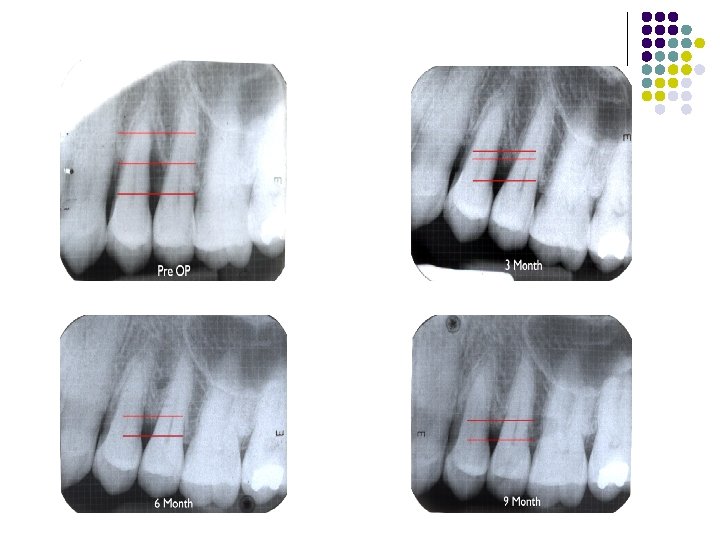

Rajesh. H (2005) : clinical study l Compared bone regenerative capacity of Chitra HABG with Osteogen (HA resorb) in 16 pts l Reduction in probing depth, gain in clinical attachment at 3, 6, 9 months l Radiograph showed evidence of bone fill

Evaluation of the results l Clinical methods– Probing- soft tissue changes (bleeding on probing) pocket depth clinical attachment level Bone levels- re-entry procedures bone sounding l Radiographic bone changes l Histological methods

Re-entry surgery l performed at 6 -12 months after the initial regeneration procedure l linear measurements in mm made along the root surface with a periodontal probe. l The distance to the base of the defect is taken relative to a fixed landmark, such as CEJ